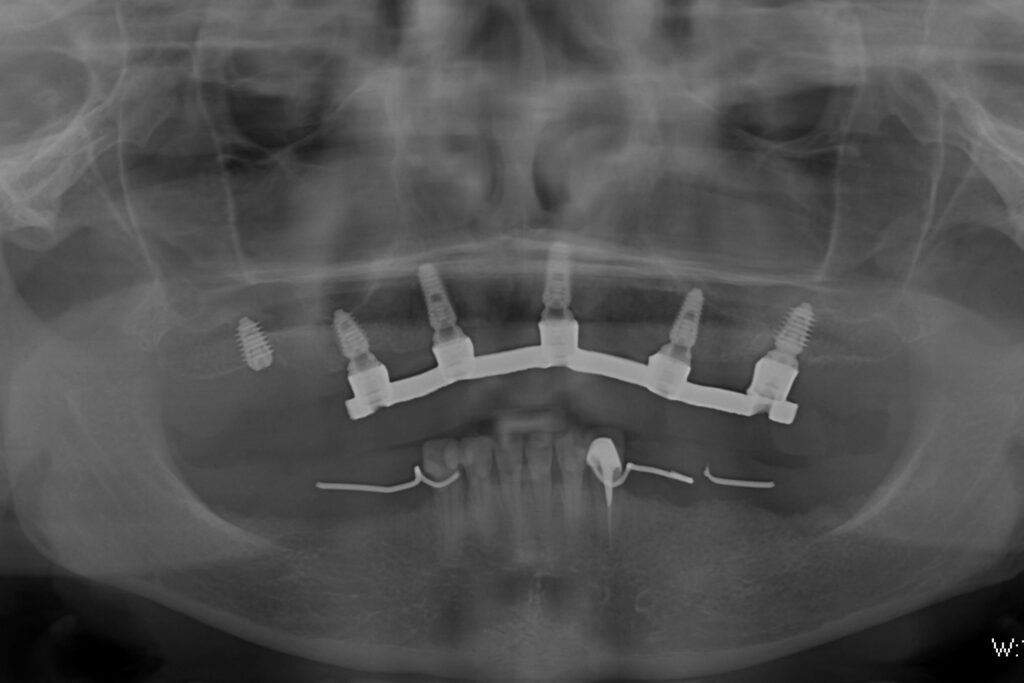

После проведенной консультации было принято решение о проведении комплексной имплантации по системе All-on-6.

После установки 6ти имплантантов Megagen AnyRidge были сняты оттиски для изготовления металлоакрилового протеза.

Спустя 7 дней на верхней челюсти зафиксирован металлоакриловый протез из 13 зубов с опорой на 5ти дентальных имплантатах.

(Не удалось добиться первичной стабильности у одного имплантата. При постоянном протезировании будут нагружены все 6 имплантатов)